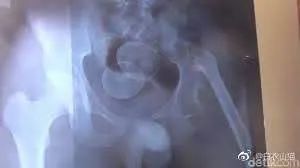

医生给他检查的时候,发现已经有腹膜炎症状,怀疑肠梗阻,拍了个片子,就是上面那个片子:一条大黄鳝在肚子里。

考虑到他已经有腹膜炎的症状,说明肠子已经有个地方破了。只能动手术了。

把肚子打开后,发现大肠破了个洞,黄鳝的头,就在那个洞里。他肚子里都是大便。他的肠子水肿很厉害。黄鳝堵住了大肠,肠梗阻,导致大肠坏死穿孔了。